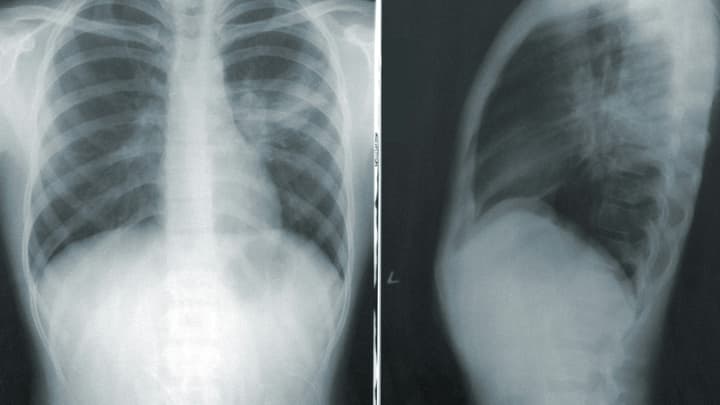

Przyczynami wtórnego błoniastego kłębuszkowego zapalenia nerek są sarkoidoza, nowotwory płuc i żołądka, wirusowe zapalenie wątroby typu B i C, toczeń rumieniowaty układowy oraz niektóre leki.